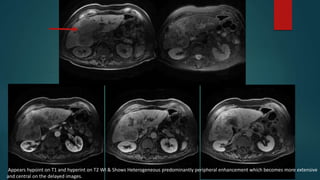

MRI

ON MRI FLC SHOWS HETEROGENOUS ENHANCEMENT

WITH HYPOINT SCAR WHICH SHOWS DELAYED ENHANCEMENT

Appears hypoint on T1 and hyperint on T2 WI & Shows Heterogeneous predominantly peripheral enhancement which becomes more extensive

and central on the delayed images.